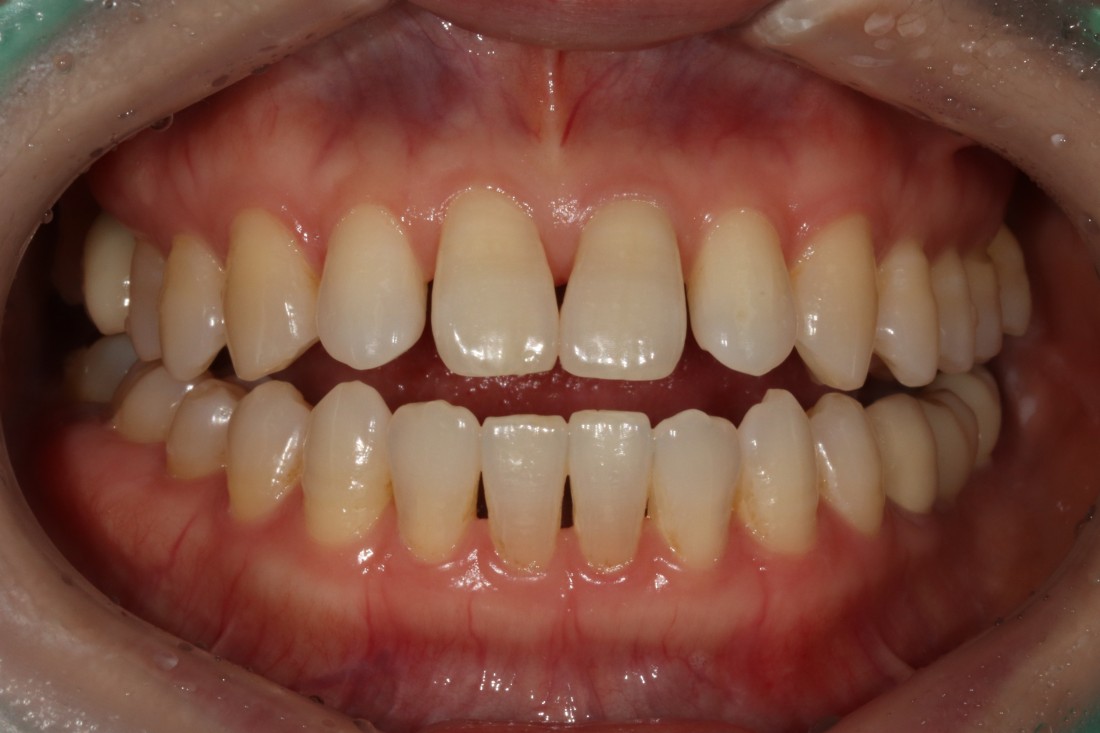

누가봐도 라미네이트 한 것 같은

뭉툭하고 새하얀 치아가 아니라,

광주 무삭제 라미네이트 치과는

'자연스러운 아름다움'을 추구합니다.

그렇기 때문에 20대부터 60대까지

정말 다양한 연령대의 고객님들이

지인 추천으로 방문해주시고 계신데요.

단순히 예뻐지기 위함이 아니라,

앞니 컴플렉스를 해결하고

치아의 기능적 요소까지 생각하여

불편함 없는 라미네이트 진료를 위해

노력하고 있습니다.